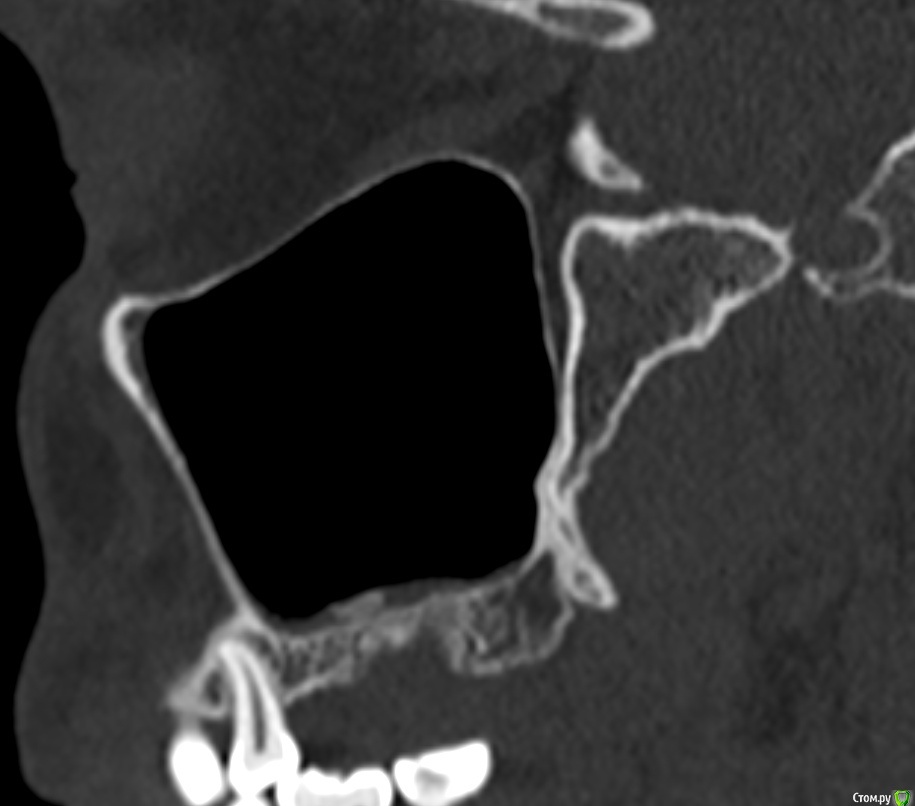

Фрагмент кости в гайморовой пазухе. Нет гноя. Причина болей?

Здравствуйте. На протяжении 5 месяцев беспокоит боль в области между левой пазухой и челюстью. Боль острая, ноющая как при боли в зубе. Верхняя 7а слева (депульпированная) удалена месяц назад, но боль только усилилась. Со временем стали болеть и все суставы в теле, в особенности руки и ноги. Выполнять простые движение стало очень больно. На КТ видны инородные фрагменты и нарушение целостности нижней стенки пазухи, но в Спб никто их не захотел удалять инородные фрагменты из-за того, что причина боли по мнению врачей не в этом. В результате боль только усиливается. Причину боли при моей картине КТ никто установить не может. Обращалась почти во все клиники. Несколько неврологов патологию лицевого нерва исключили. Все это время держится температура 37-37,5. Ощущение сильного воспалительного процесса, боль немного стихает на приеме антибиотиков, но ненадолго, примерно на неделю - две. Обычные обезболивающие совершенно не помогают. Жевать пищу очень больно, сильно рот не открыть. Слабость и нет аппетита. Может ли так организм реагировать на инородный фрагмент кости в пазухе или дело в другом? Возможно ли что есть какие-то нарушения (переломы, трещины и пр) кости, которые требуют хирургического вмешательства?Вопрос возник по той причине, что при промывании пазухи есть ощущение проникания жидкости куда-то за пределы слизистой и после промывания состояние заметно ухудшается. Если кто-то может помочь советом буду очень признательна. Есть несколько КТ 3д. https://yadi.sk/d/PX30GoO1Cn5m_w -  от 13.06.2020 (примерно сразу после появления болевого синдрома), https://yadi.sk/d/bm7FD9SYVw2-Gw- сразу перед удалением зуба,  https://yadi.sk/d/fbaOTQT2-ya4xQ - КТ пазух от 21.11.2020 (то что есть на сегодня).